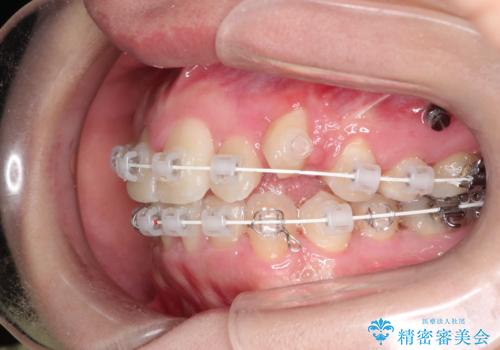

犬歯が変な位置にある 抜歯矯正により正しい位置へ

左上の犬歯が通常の位置より、かなり上方にあり、乳歯の残存と前歯のがたつきがありました。

残った乳歯と上下左右の永久歯を1本ずつ抜歯して、ワイヤーにて矯正することとしました。

犬歯も通常の位置にまで移動することができ、口元もすっきりすることができました。